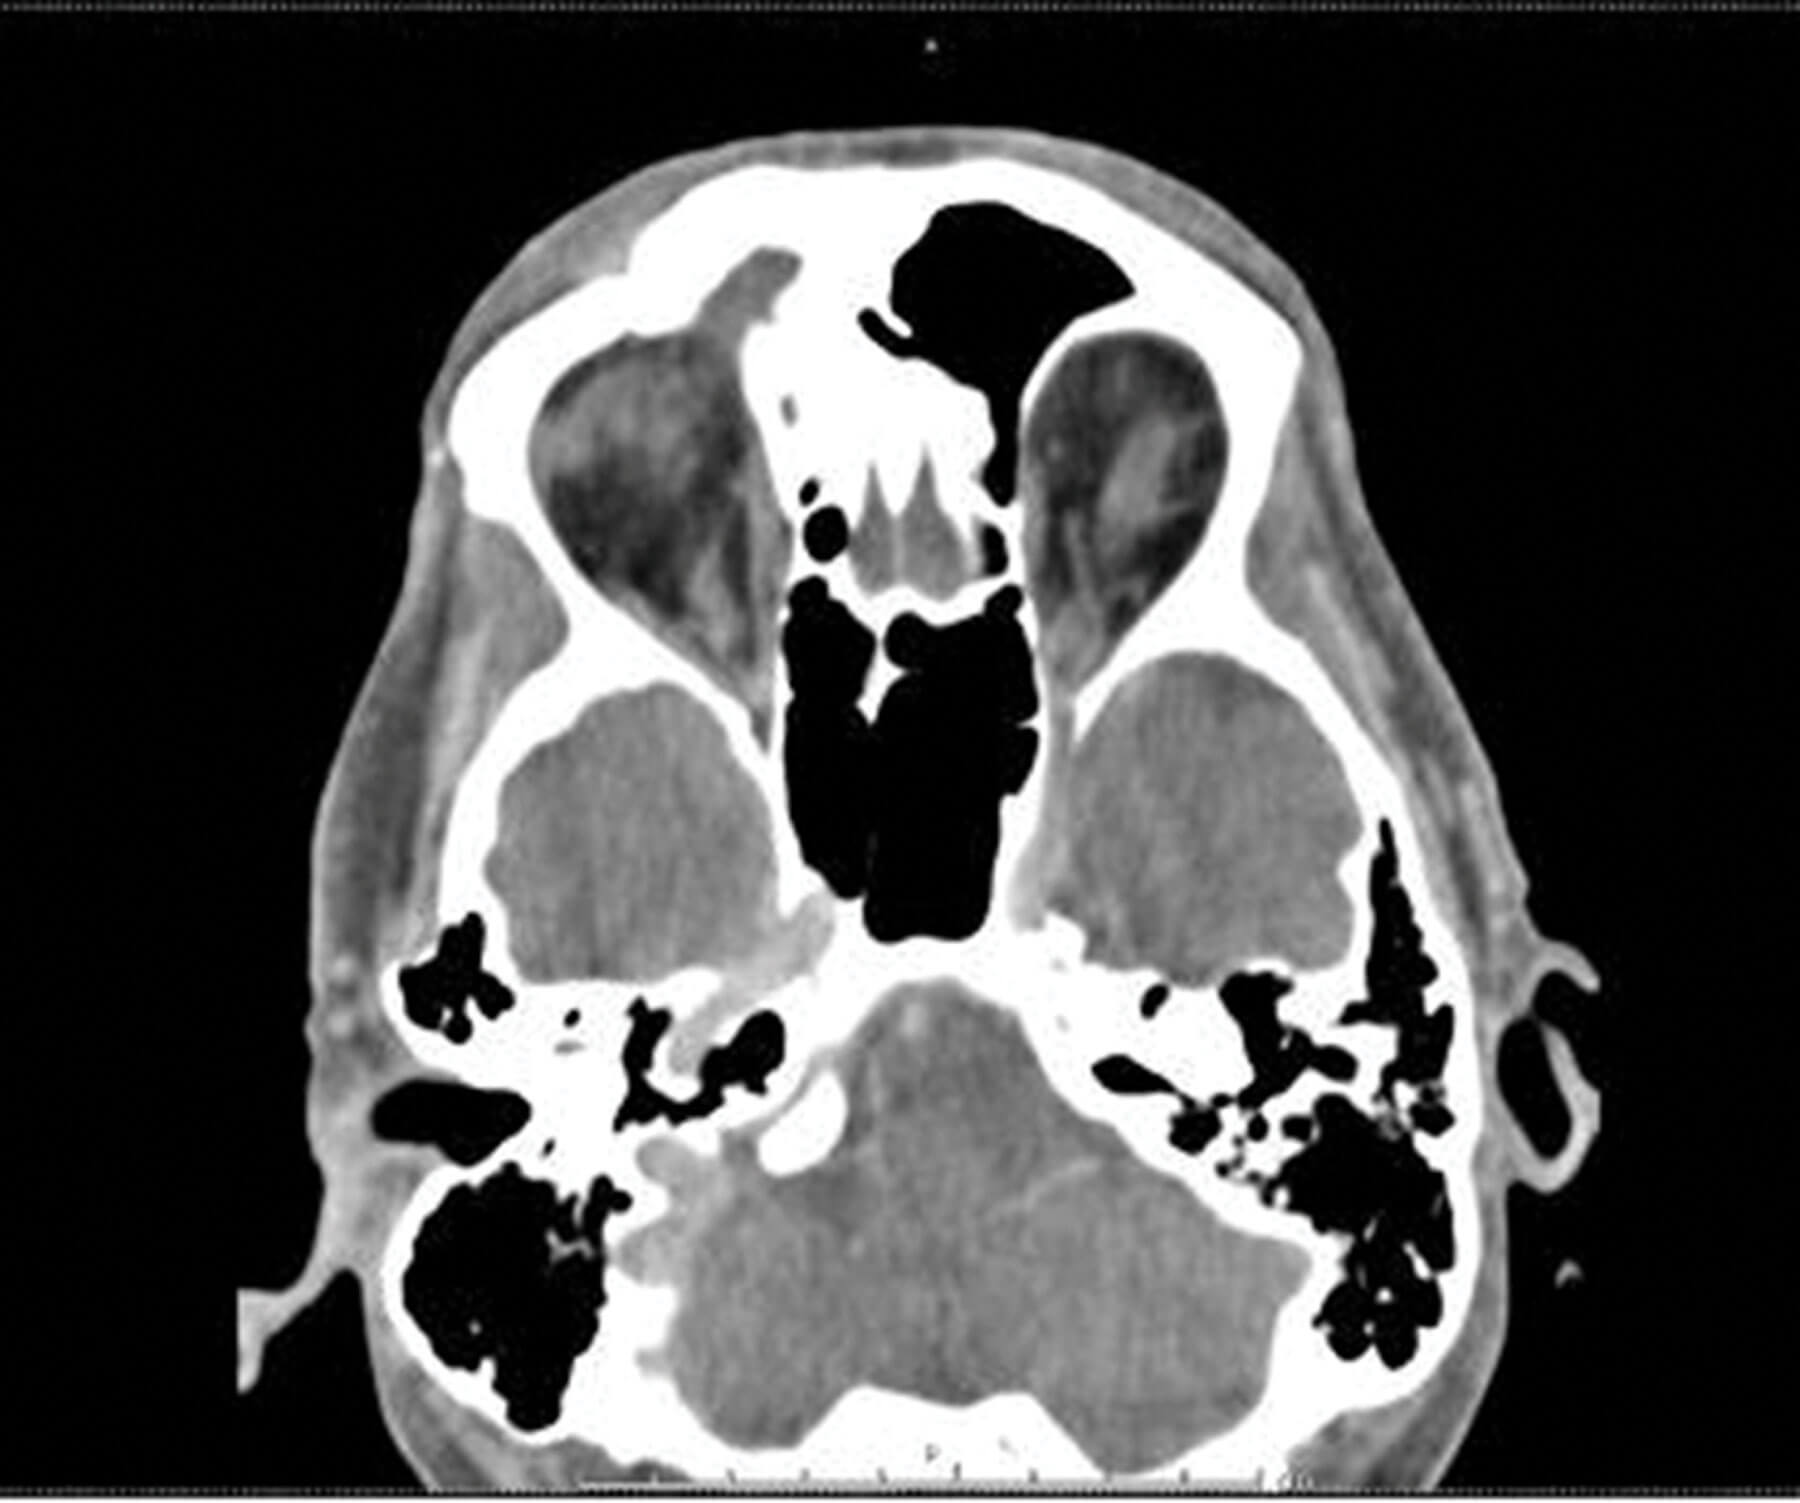

Figure 4: CT scan six months after, showing hyper-ossification of

the frontal sinus wall with reduction of expansion of the sinus.

After an ENT referral and endoscopy, the patient was advised to have a DRAF III procedure. However, he refused as he was completely asymptomatic post biopsy and sinus irrigation. Within a couple of weeks, the patient had a complete resolution of the ptosis and the skin lesion (Figure 1c). Follow-up CT scans, done six months later, showed hyperostosis of the right frontal sinus walls, with less expansion of the sinus (Figure 4). The patient’s consent was obtained for information access and publication.